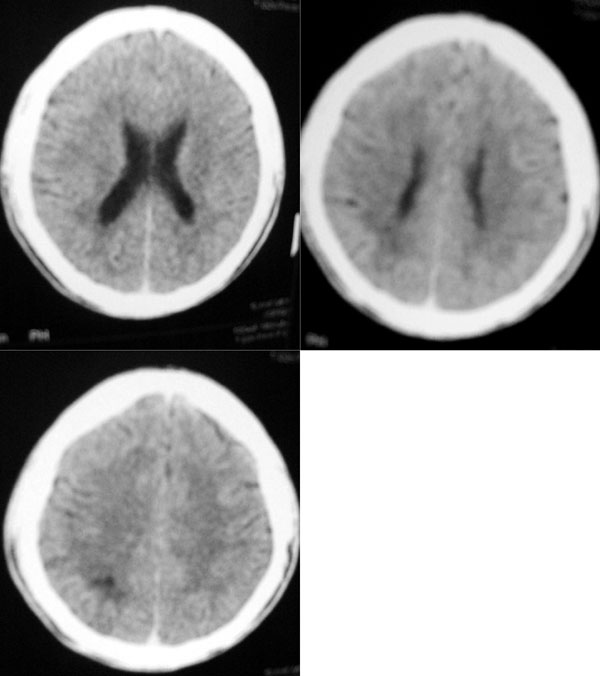

妄想,想打人一月,三年前被人砍伤,头颅ct当时正常

右枕顶叶见斑片状低密度区,边界清楚,有轻度负占位效应。

考虑:脑软化灶。

支持右顶枕叶脑软化灶。

右侧枕叶囊实混杂密度病灶,病灶的形态非常符合胶质细胞瘤的。只是怎么会没有占位效应,反而有负性吸引力,导致侧脑室后角轻度扩大?

“妄想,想打人一月,三年前被人砍伤,头颅ct当时正常”,首先可以排除动静脉畸形,难道是软化灶?很奇怪的病例,建议增强或mri。

我想问一下大家颞枕叶交界处和颞顶叶的那一小片状低密度影都考虑软化灶么??

楼主又补充了3张图片,显示右侧顶叶也有类似的病灶,而且与枕叶病灶间相连。再结合病人临床症状,这就彻底不能用软化灶来解释了,考虑肉芽肿性病变,的确需要增强或mri检查!

结合临床有精神症状,考虑炎性肉芽肿,建议增强,看有没有结节状强化。

右侧顶枕叶不规则、不均匀等低低密度,周围有轻度负占位效应,考虑动静脉畸形,建议增强检查。

右枕顶叶见斑片状低密度区,内见脑回样致密影,边界清楚,有轻度负占位效应。考虑: 动静脉畸形。建议 mri

我考虑软化灶,至于是外伤,还是动静脉畸形出血之后形成的软化灶,我趋向于外伤引起的,三年前头颅ct未见异常,有可能外伤当时还没发生出血,这在临床工作中也比较常见,假如用动静脉畸形解释的话,那这个软化灶就是三年之前那次外伤之后到现在这段时间发生的,而且病人没有多大的症状,这种解释好象有点勉强